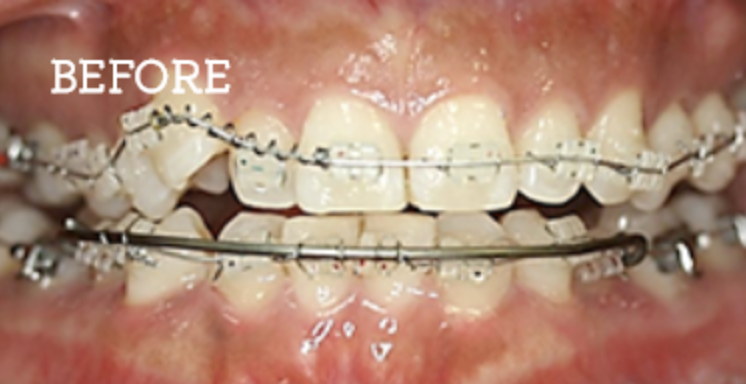

健康な歯をできるだけ残した矯正治療

当院では非抜歯の矯正も可能です。(※審美性を優先する場合は抜歯が必要な場合もございます。)

治療方法としては、歯列の幅を広げて隙間を確保し、歯を揃える手法を採用しています。特にV字型や方形型の歯列の方は、非抜歯でも矯正可能な方が多いです。

患者様のご要望に合わせて、最適な提案を行い、納得いただいた上で治療を進めるよう努めています。